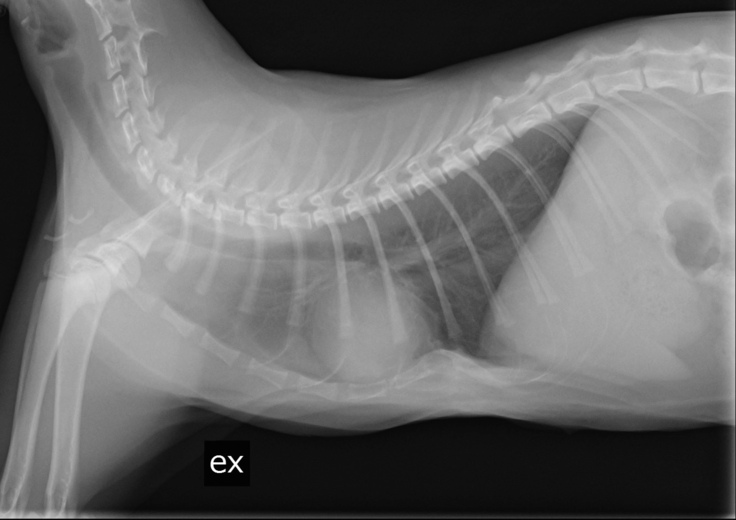

現状報告②検診結果をご報告します

本日術後の検診に行ってきました。

胸骨は正常な位置に留まっており、

経過は良好なようです。

今回の検診で撮影したレントゲン写真と診療明細書の写真を添付しておきます。

☟息をはいている所です